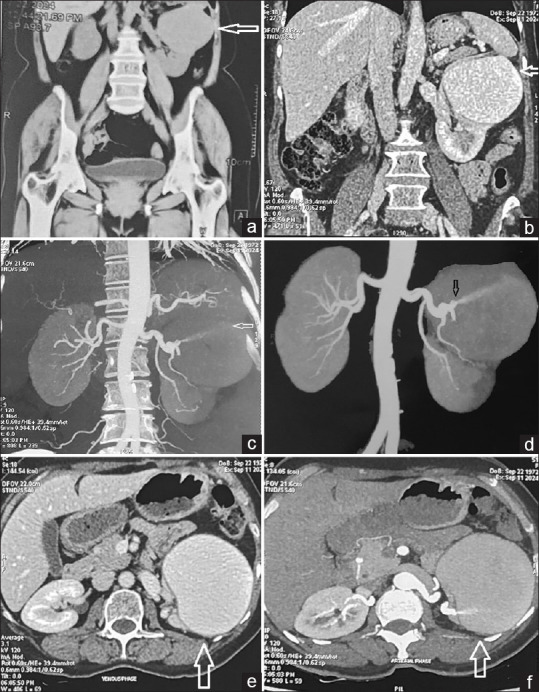

A 52-year-old female presented with a history of left partial nephrectomy performed 1 year ago for a left renal mass. She was asymptomatic and was under post-operative follow-up. A contrast-enhanced computed tomography scan of the abdomen was obtained which revealed a large renal artery pseudoaneurysm (of size 79 mm ×67 mm ×78 mm). In view of large size, therapeutic angioembolization was performed safely without any post intervention complications.